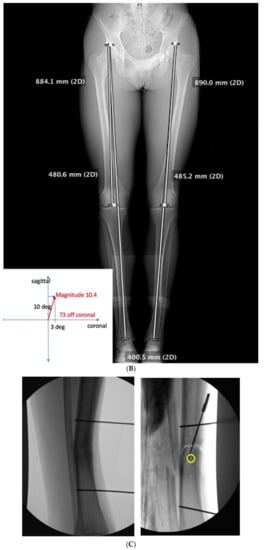

3.2. Case 2-Single-Plane Correction with Plate Fixation: Tibia

A young adult college baseball player presented with symptoms of lateral proximal knee pain and a feeling of knee instability 8 months after sustaining a closed fracture of the tibia, initially treated closed with casting (Figure 7A). The patient underwent a workup including full-length films, knee MRI, and local anesthetic test injection of the proximal tibiofibular joint (relieving knee pain). The CORA analysis revealed a recurvatum deformity of 10 degrees and varus deformity of 3 degrees, with translation in the coronal plane. Full-length alignment film of the pelvis and lower extremity confirmed coronal translation with mild varus angulation (Figure 7B). The true plane of deformity was calculated approximately 75 degrees from the coronal plane (15 degrees off-sagittal) with a magnitude of between 10 and 11 degrees.

Figure 7.

(A) A young adult college baseball player sustained a closed tibia fracture with intact fibula, treated closed. The patient developed a recurvatum deformity with pain at the proximal and distal tibiofibular joints. (B) The patient demonstrated mechanical axis lateralization due to coronal plane translation with slight varus. The plane of deformity was calculated as 73 degrees off of the coronal plane. (C) The patient underwent focal dome osteotomy at the CORA (yellow circle) in the plane of maximum deformity. (D) Dual plate compression was used. Angulation and translation were simultaneously corrected. (E) Final follow-up 9 months: anteroposterior, lateral, and oblique films show the osteotomy healed. Tibiofibular joint pain resolved after osteotomy. Patient returned to college-level baseball.

A focal dome was chosen to correct the varus recurvatum and translation. The surgical approach was an anterior approach over the anterior compartment, elevating the tibialis anterior from the lateral tibia to allow safe access to the plane of the deformity. The fibula was osteotomized near the level of the tibia through a separate lateral approach. The plane of maximum deformity was assessed intraoperatively and confirmed the preoperative calculations. The ‘no deformity’ view on fluoroscopy was located, with the maximum plane orthogonal to this. It is in this plane that the drill bit at the CORA is directed, and this is especially important if correcting a translation. The arc of the osteotomy was drawn using a parallel drill guide with one bit centered at the CORA (Figure 7C).

The angulation and translation were simultaneously corrected. Dual medial–lateral plates were used to counteract the lateral gap forming with medial plate compression. Hence, balanced compression from the medial and lateral plates restored the alignment and provided absolute stability (Figure 7D). The patient had immediate relief of knee pain after correction. The soft tissue and osteotomy healed without incident (Figure 7E).